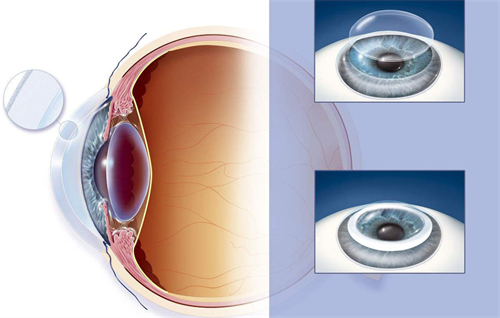

首先,需要明确的是,高度近视1500度并非手术的肯定禁忌。在医学技术不断发展的今天,有多种手术方式可以考虑用于矫正高度近视。其中,眼内屈光手术,特别是人工晶体植入术(ICL),被认为是针对高度乃至***度近视患者的有效选择。

人工晶体植入术(ICL)通过在眼内植入一个特殊的人工晶体来矫正视力,这种手术避免了切削角膜的风险,且对角膜厚度没有严格要求。对于近视度数高达1500度的患者来说,这种手术方式可能更为适合。ICL手术适应的近视度数范围广泛,通常可矫正300度到2300度的近视,以及600度以下的散光。